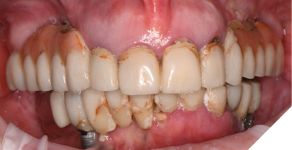

A 55-year-old woman presented with a chief complaint of wanting to complete the treatment of her maxilla and mandible that had begun elsewhere a number of years ago. The patient reported that she had several implants placed and provisional bridges inserted a number of years ago. A review of her medical history revealed no significant findings. A clinical exam was performed, and the following data was collected: a full mouth series radiographic survey, a cone beam CT scan, intraoral surfaces scans, full face and intraoral photos (Figs. 1,2,3).

Fig. 1

Fig. 2

Fig. 3

The data recorded during the clinical exam in conjunction with the FMS xrays and CT scan data were analyzed, and a diagnosis was made as to the viability of the patient’s existing teeth. A virtual diagnostic wax up was completed using prosthetic planning software (ExoCad) (Figs. 4A, 4B). The .STL file of the virtual wax up was integrated with the CT scan data in implant surgical planning software (3Shape Implant Studio) and a surgical plan was designed (Figs. 5A, 5B). The viability of this surgical plan was then evaluated in conjunction with the previously determined prognosis of the patient’s existing dentition and surrounding periodontium, and a treatment plan was formulated. The plan with the anticipated predictability of achieving the planned result was presented to the patient. The patient approved the treatment plan.